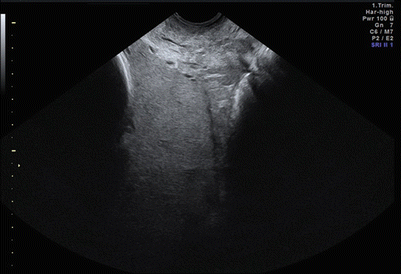

Role of transperineal sonography in diagnosis of placenta previa ...

Comparison of transabdominal and transvaginal sonography in the ...

Basic Obstetric Ultrasound - Department of Obstetrics and ...